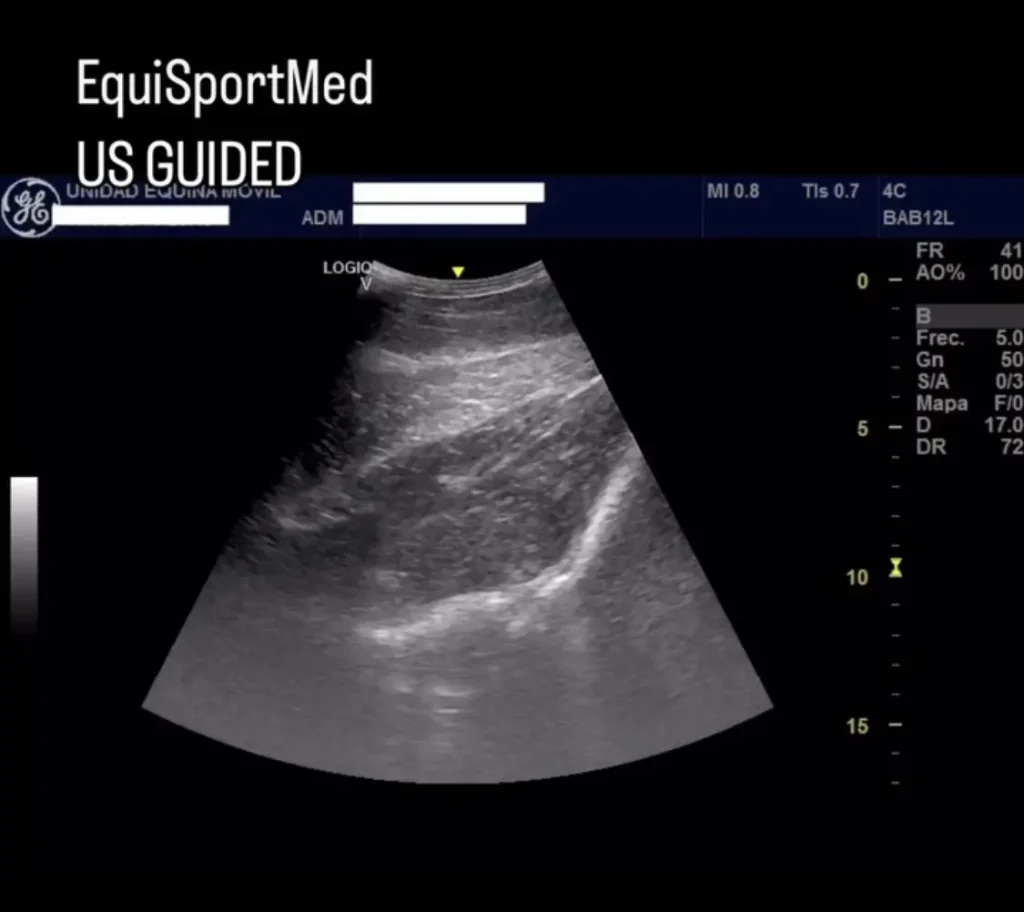

Advanced Diagnostic Imaging

We carry out diagnostic tests such as scintigraphy, magnetic resonance imaging, among others, in collaboration with equine veterinary hospitals.